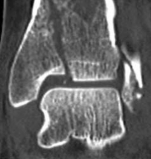

Fig 2.2-3a–h A CT scan with 3D reconstruction.

a–d Sagittal (a–b), coronal (c), and axial (d) images demonstrate displaced posterior, anterolateral, and medial fracture fragments resulting in intraarticular step and gap. The incongruent tibiotalar joint is best appreciated on the sagittal scan.

e–h The 3D reconstructed images show the external fracture anatomy and general alignment.